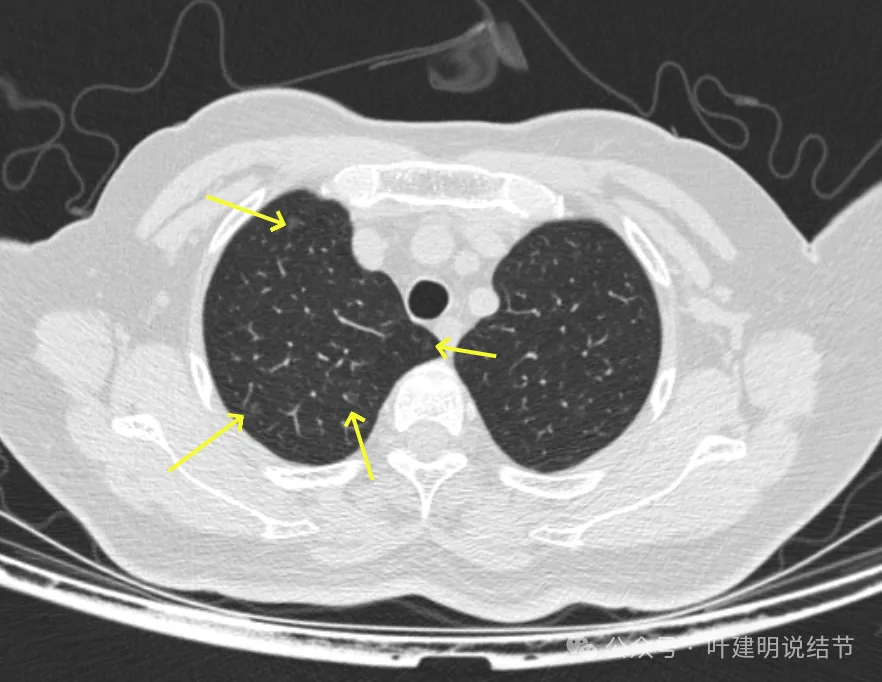

病灶7-9:右肺上叶淡磨玻璃结节,轮廓较清。

病灶15-18:右上叶淡磨玻璃结节,轮廓较清,有的界限稍不清。